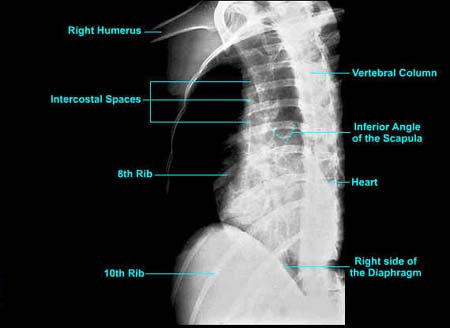

Intercostal image